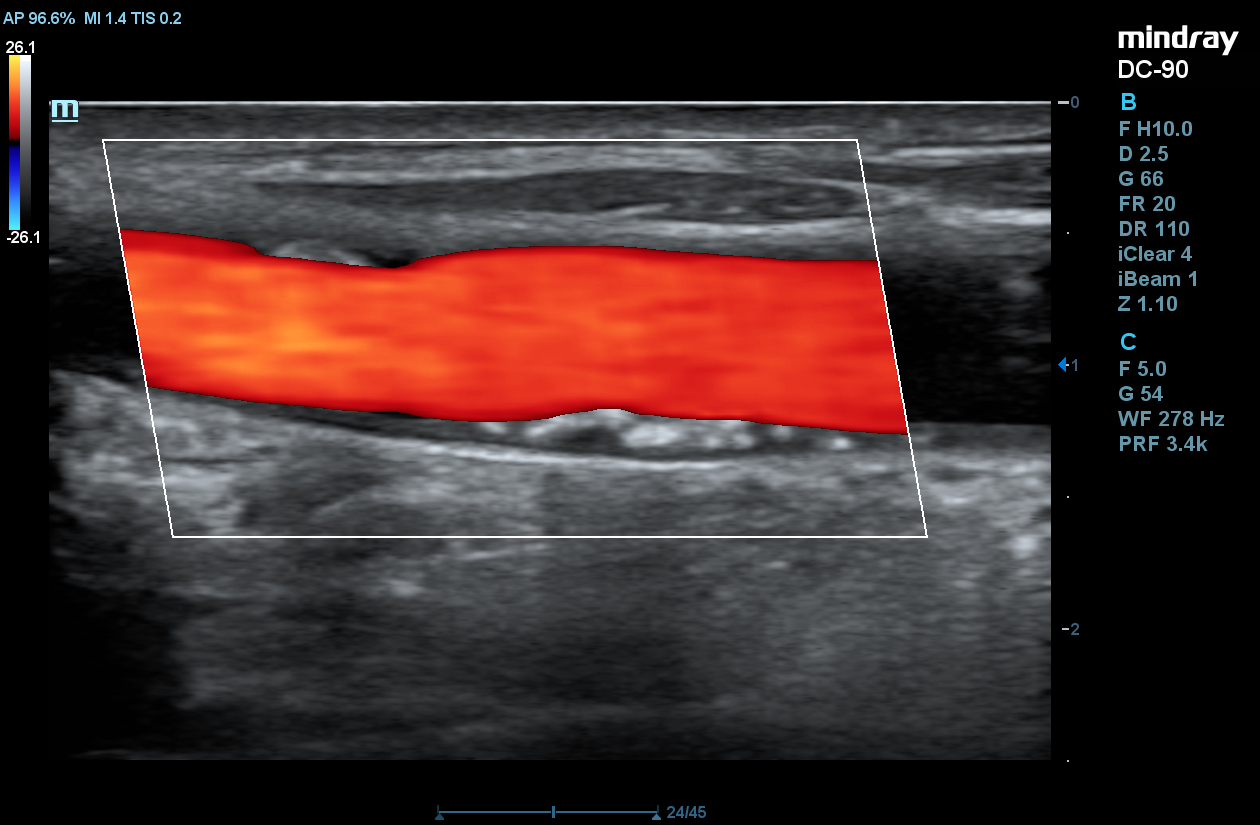

STE

Mindray’s Sound Touch Elastography (STE) utilizes exclusive Ultra-Wide Beam Tracking technology to provide comprehensive quantification metrics and dynamic visual display of tissue stiffness for enhanced diagnostic confidence. Using real-time and rapid data acquisition from a wide beam single pulse, STE is designed to reduce noise caused by motion artifact for improved efficiency and accuracy of measurements.